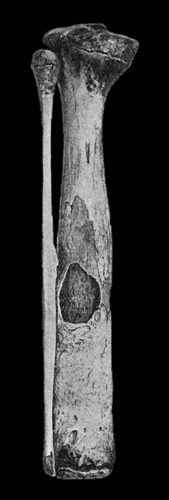

19.Tibia and Fibula, showing changes due to Chronic Ulcer of Leg 80

120.Segment of Tibia resected for Brodie's Abscess 449